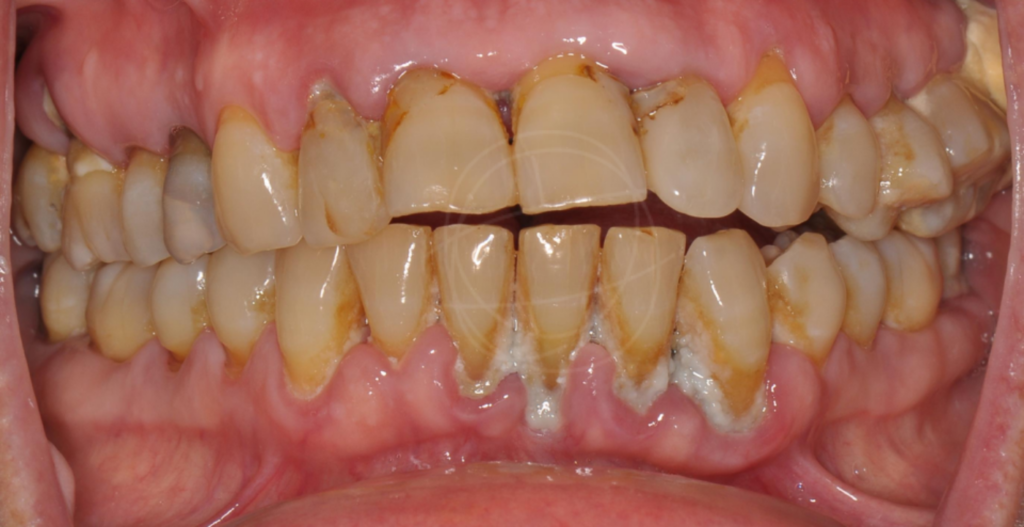

Τα οδοντικά εμφυτεύματα έχουν μεταμορφώσει τη σύγχρονη οδοντιατρική από την ανακάλυψη της οστεοενσωμάτωσης από τον Per-Ingvar Brånemark το 1952, της διαδικασίας όπου το τιτάνιο συντήκεται φυσικά με το οστό. Αυτή η ανακάλυψη οδήγησε στα πρώτα επιτυχημένα εμφυτεύματα τιτανίου το 1965, αποδεικνύοντας τη μακροπρόθεσμη σταθερότητα και ασφάλειά τους. Σήμερα, τα οστεοενσωματωμένα οδοντικά εμφυτεύματα τιτανίου αποτελούν μια αξιόπιστη, ευρέως χρησιμοποιούμενη λύση για την αποκατάσταση ελλειπουσών δοντιών και τη θεραπεία σύνθετων στοματικών παθήσεων.

Είναι σήμερα η πιο σύγχρονη και αξιόπιστη λύση για να αντικαταστήσουμε δόντια που έχουν χαθεί ή έχουν καταστραφεί. Σε σχέση με τις παραδοσιακές μασέλες ή τις γέφυρες, προσφέρουν μια μόνιμη, σταθερή και πολύ

Σε αντίθεση με τις γέφυρες, που συχνά απαιτούν τρόχισμα των διπλανών φυσικών δοντιών και δεν εφαρμόζουν πάντα με απόλυτη ακρίβεια, τα εμφυτεύματα λειτουργούν αυτόνομα. Έτσι προστατεύεται η συνολική στοματική υγεία και αποκαθίσταται πλήρως η λειτουργία του στόματος, με αποτέλεσμα που διαρκεί.

Τι είναι ένα οδοντικό εμφύτευμα;

Ένα οδοντικό εμφύτευμα είναι μια «τεχνητή ρίζα» από βιοσυμβατό τιτάνιο, που τοποθετείται χειρουργικά στο οστό της γνάθου. Πάνω του στηρίζεται μια στεφάνη (το «τεχνητό δόντι»), η οποία μοιάζει και λειτουργεί όπως ένα φυσικό δόντι. Γι’ αυτό και συχνά τα εμφυτεύματα θα τα ακούσετε ως «βιδωτά» ή «φυτευτά» δόντια.